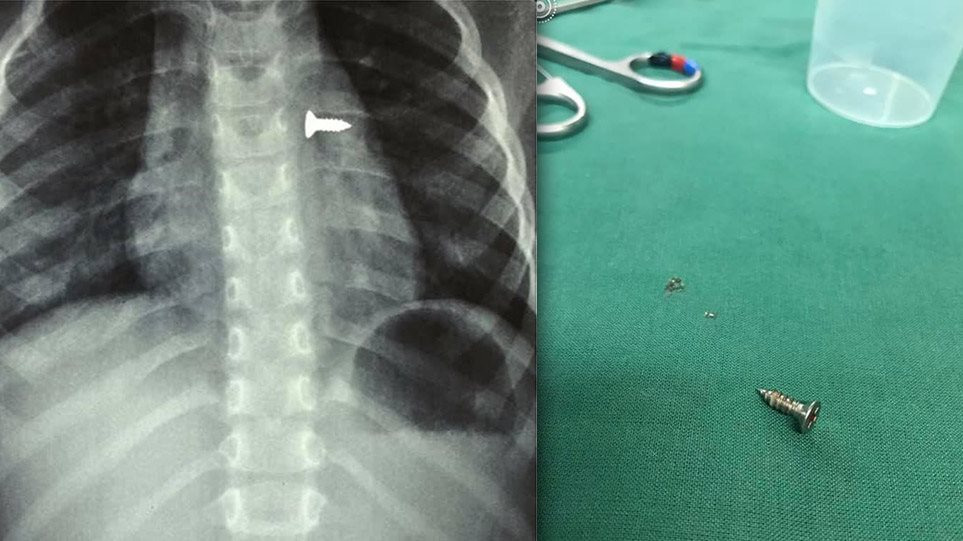

Σοκ προκαλούν οι ακτινογραφίες από ένα κοριτσάκι που κατάπιε βίδα, η οποία κατέληξε στον αριστερό του πνεύμονα.

Σύμφωνα με τα όσα έκανε γνωστά ο αναπληρωτής καθηγητής ΩΡΛ της Ιατρικής Σχολής Κρήτης, Μανώλης Προκοπάκης, χθες μεταφέρθηκε σε νοσοκομείο του Ηρακλείου ένα τρίχρονο κορίτσι το οποίο κατάπιε μία βίδα.

Αμέσως του έγιναν ακτινογραφίες που έδειξαν πως η βίδα βρισκόταν στον αριστερό πνεύμονα του παιδιού.

Οι γιατροί άμεσα οδήγησαν το κορίτσι στο χειρουργείο και μετά από αρκετή ώρα κατάφεραν να αφαιρέσουν την βίδα.

Ο κ. Προκοπάκης σε ανάρτησή του στα social media ανέφερε:

«Πολύ επείγον χειρουργείο! Πριν από λίγο. Αφαίρεση βίδας από αριστερό βρογχικό δέντρο τρίχρονου κοριτσιού. Πολύ επικίνδυνο…».